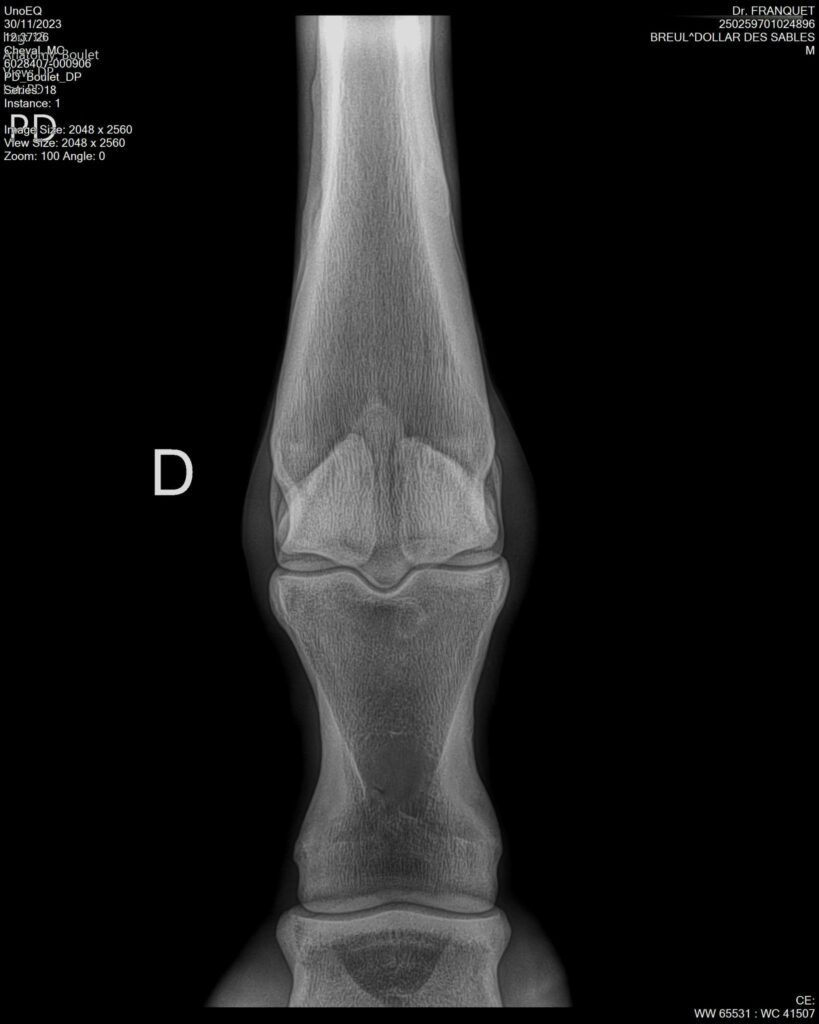

DOLLAR DES SABLES, Selle Français, hongre, 12 ans par DOLLAR DE MURIER x ABKE (ACORADO). Classé 135 avec professionnel à fait 125 avec amateur, récemment classé sur amateur 1GP 120. Très beau modèle ! Gentil cheval, respectueux avec des moyens et du sang. Transport OK, maréchalerie OK, santé RAS, Bilan clichés radios OK.

RADIOS